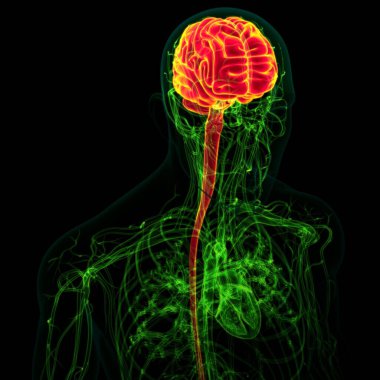

Tıbbi Konsept için sinir sistemi anatomisi olan 3D İnsan Beyni

MaviGrafikselresimlemeŞeffafİnsanSağlıkBaşıİlaçerkekkordonüç boyutlubiyolojikHücregövdeHastalıkİstihbaratİçeridebiyolojiBilimSistemAcıorgzihinomurgaelektronİşaretgörüntü oluşturmaanatomiomurilikbeyinMerkezGerginNörolojimikroskobikBeyin fırtınasıSıhhiyeanatomikSinirbeyincikcerebra3d oluşturmaüzerine siyahsinir hücresiBenzer İçerikler